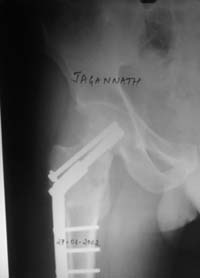

При явно выраженном варусе и флексионных состояниях после сросшихся переломов шейки бедра у молодых рекомендуется реконструктивная операция по исправлению варуса для предотвращения раннего деформирующего артроза, приводящего в результате переднего импинжмента, как показано на снимке.

Межвертельная вальгусная остеотомия представляет наименьший риск среди всех реконструктивных операции в проксимальной части бедра, создавая наилучшие биомеханические условия (увеличивается сила абдукторов, увеличивается сила суставной реакции, уменьшение рычага моментов абдукторов и уменьшение скольжения) и при меньшем риске повреждения кровоснабжения головки, где обычно в 90% случаях достигается отличный результат при применении метода для лечения ложных суставов шейки бедра.

По моему, 120 градусная угловая пластина blade plate решит все проблемы, только необходим предварительный расчет угла остеотомии, и во время фиксации пластины не забыть латерализацию бедра, иначе ось конечности от варуса перейдёт в нежелательный вальгус.

Для предупреждения вальгуса клинок пластины берется на 10-12 мм длиннее чем предварительный туннель на головке, тогда во время

фиксации за бедро пластина автоматически приблизит бедро и происходит латерализация бедра. Если между клинком и латеральным кортексом бедра положить частицу кости от остеотомии тогда образуется дополнительная компрессия на фокусе несращения.

Здесь мои диаграммы для расчета угла остеотомии и латеризации бедра.